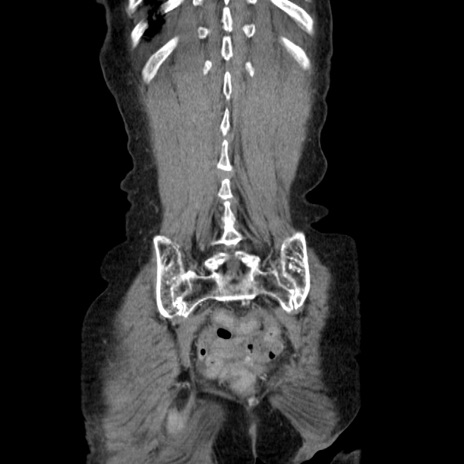

症例25(冠状断像)

【症例】80歳代女性

【主訴】胸のつかえ感

【現病歴】約9時間前に食後から胸のつかえた感じあり、嘔吐あり、来院。

【既往歴】胃癌(全摘)、胆摘、虫垂炎

【身体所見】心窩部に圧痛あり、反跳痛なし。

【データ】WBC 5700、CRP 0.05